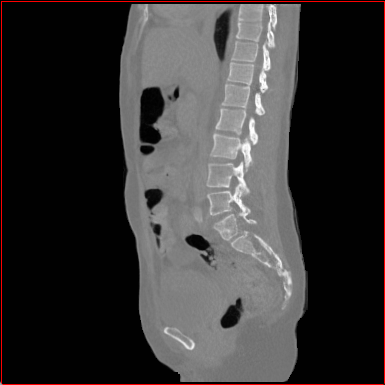

MAISI-v2 generalizability:

Figure 4 shows qualitatve results of MAISI-v2 ControlNet for different body regions and voxel sizes.

Head Region

1.1×1.1×1.11.1\times 1.1\times 1.1

mm

256×256×256256\times 256\times 256

Chest Region

1×1×11\times 1\times 1

384×384×384384\times 384\times 384

Abdomen Region

1×1×0.71\times 1\times 0.7

512×512×768512\times 512\times 768

Refer to caption

Figure 4: MAISI-v2 segmentation-guided results for small to large volume size and three different regions.